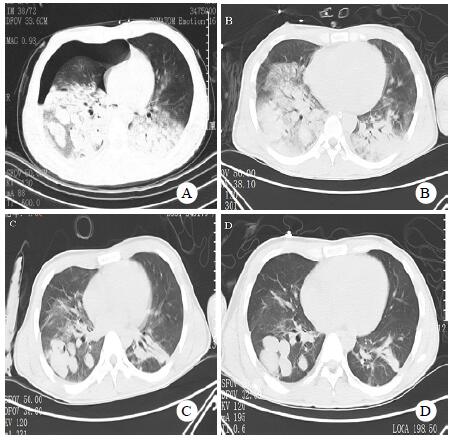

患者,男性,24岁,因“外伤致全身多处疼痛流血4 h,伴咯血”于2019年8月27日入院。患者入院前4 h前骑摩托车时发生车祸,与护栏及地面猛烈撞击,当即感到胸部、右肩、右臂、右髋、右眼眶等全身多处疼痛伴流血,并咯出大量鲜红色血液,伴有胸闷、气急,呼吸困难,无意识不清,无腹痛,无呕吐呕血,无血尿等。120救护车送当地医院急诊就诊,行CT检查示“颅脑未见明显外伤性征象,胸部多发肋骨骨折,右侧液气胸,两肺挫伤,右肺撕裂伤,肺内多发血肿形成,右侧锁骨、肩胛骨及颈7-胸7椎体横突骨折。腹部未见明显外伤性征象,附见右侧髂骨骨折”。因咯血量大,氧饱和度不佳,血压下降,转来嘉兴市第一医院创伤中心。入院时患者意识模糊,烦躁,体温36.2℃,脉搏135次/min,呼吸34次/min,血压60/32 mmHg(1 mmHg=0.133 kPa),SPO2 75%,右眼眶皮肤裂伤伴活动流血,全身多处皮肤擦伤,右前臂畸形,颈软,气管左偏,颈静脉无怒张。胸部视诊:前胸部皮肤挫裂伤伴活动流血,右胸饱满,右肋间隙增宽,左胸无畸形,左肋间隙正常,右侧呼吸运动减弱,左侧呼吸运动正常;触诊:双肺未扪及胸膜摩擦感,右胸扩张度减小,左胸廓扩张度正常;叩诊:左肺清音,右肺过清音;听诊:右肺呼吸音消失,左肺呼吸音粗糙,闻及湿性啰音,未闻及胸膜摩擦音。心率135次/min,心律齐,心音正常,未闻及病理性心脏杂音。腹平软,无压痛,肝脾肋下未及,移动性浊音阴性,肠鸣音4次/min。骨盆挤压痛阳性,双下肢无畸形,四肢肌力检查不配合,病理征阴性。血常规示白细胞计数27.4×109/L,中性粒细胞百分比83.5%,血红蛋白106 g/L,血小板181×109/L;血气分析示氧分压(PO2)60.9 mmHg,二氧化碳分压(PCO2)35.4 mmHg,碱剩余(BE)-10.4 mmol/L,pH 7.266;凝血功能示:凝血酶原时间(PT)24.3 s,活化部分凝血活酶时间(APTT)74.4 s,纤维蛋白原(FIB)1.02 g/L。立即予以气管插管、胸腔闭式引流、深静脉穿刺置管、去甲肾上腺素针0.1~0.2 μg/(kg·min)微泵维持升压、输血、补液、止血、镇痛等治疗,收住本院EICU。入院诊断为失血性休克、肺挫裂伤、咯血、呼吸衰竭、多发肋骨骨折、液气胸、右锁骨骨折、右肩胛骨骨折、右尺骨骨折、右髂骨骨折、颈椎横突骨折、胸椎横突骨折。入EICU后患者100%吸入氧体积分数下氧饱和度约为80%,血气分析示PO2仅55 mmHg左右,予以更换双腔气管插管,去甲肾上腺素稀释液气管套管内滴入止血,患者氧饱和度短暂上升后又再下降,双侧气管套管腔内均有大量新鲜血液咯出,量约600~1 000 mL/d。胸外科、介入科及麻醉科会诊均认为患者双肺均有严重挫裂伤,如开胸手术治疗需要切除的肺组织较多,但患者氧合情况极差,预计无法耐受手术,建议介入下行肺动脉栓塞治疗。但介入治疗后患者病情仍未见好转,咯血量未见减少,氧合指数(PaO2/FiO2)持续下降至50 mmHg以下,血乳酸上升至7.6 mmol/L。入院第2天与家属商议后决定行体外膜肺氧合(extracorporeal membrane oxygenation,ECMO)治疗,采用V-V模式,右股静脉引血置管20 Fr,右颈内静脉回血置管19 Fr,使用ROTAFLOW离心泵及QUADROX PLS氧合器,转速3 500 r/min,血流量4 L/min,氧流量5 L/min,患者氧饱和度上升至90%~95%。预冲时预冲液中加入5 000 U肝素,随后ECMO运行第1~5天均无肝素抗凝,5 d后患者咯血明显减少,逐渐使用小剂量肝素抗凝维持激活全血凝固时间(activated clotting time of hole blood,ACT)在110~150 s。8 d后患者病情好转停ECMO,13 d后停机械通气,15 d后转普通病房并行骨折切开复位内固定手术,30 d后痊愈出院。救治过程中共计输注悬浮红细胞23 U,血浆3 900 mL,血小板10 U。患者治疗期间胸部CT演变见图 1。ECMO技术经过本院医学伦理委员会审批,审批号:LS2019-195。

| A:入院当天;B:入院11 d;C入院21 d;D入院30 d 图 1 患者胸部CT演变 |